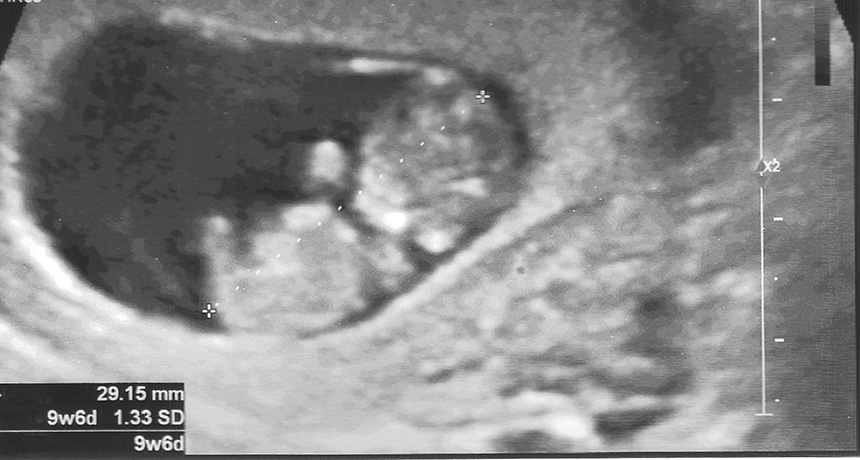

EARLY DAYS This ultrasound is of a 9-week-old fetus. A new test using fetal cells obtained from a Pap smear can scan a fetus’s genome as early as five weeks.

gulencnn/iStockphoto